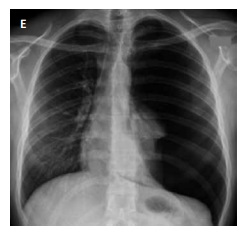

Correlacionar imagens tomográficas com quadro clínico.

A homem de meia idade, tabagista, dispneia progressiva aos esforços com meses de evolução, espirometria com vef1/cvf > 70, estertores predominando no final da inspiração ao exame físico

B mulher de 67 anos de idade, tabagista, tosse crônica, dispneia aos esforços, policitemia no hemograma, tempo expiratório prolongado, ausculta pulmonar com murmúrios vesicular reduzidos globalmente

C homem de 68 anos de idade, hipertenso mal-controlado, cardiopata, piora de dispneia, edema de membros inferiores, ortopneia, ausculta abolida em bases e estertores em ápice pulmonar

D jovem de 27 anos de idade, com antecedente de hepatopatia em investigação, com relatos de dispneia durante os esforços físicos, ausculta com murmúrios vesiculares diminuído em bases pulmonares